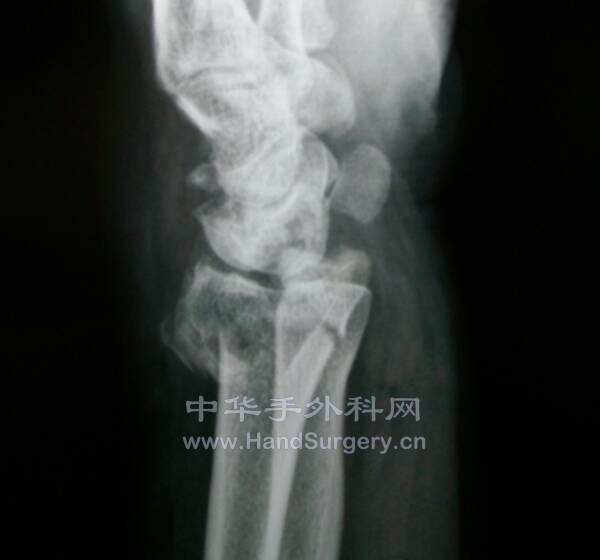

桡骨远端骨折,远端粉碎或太短,不能接受钢板远端钉排

克氏针+外固定支架是绝佳选择

这里就是其中一个典型病例

桡骨远端骨折C3型合并舟骨骨折